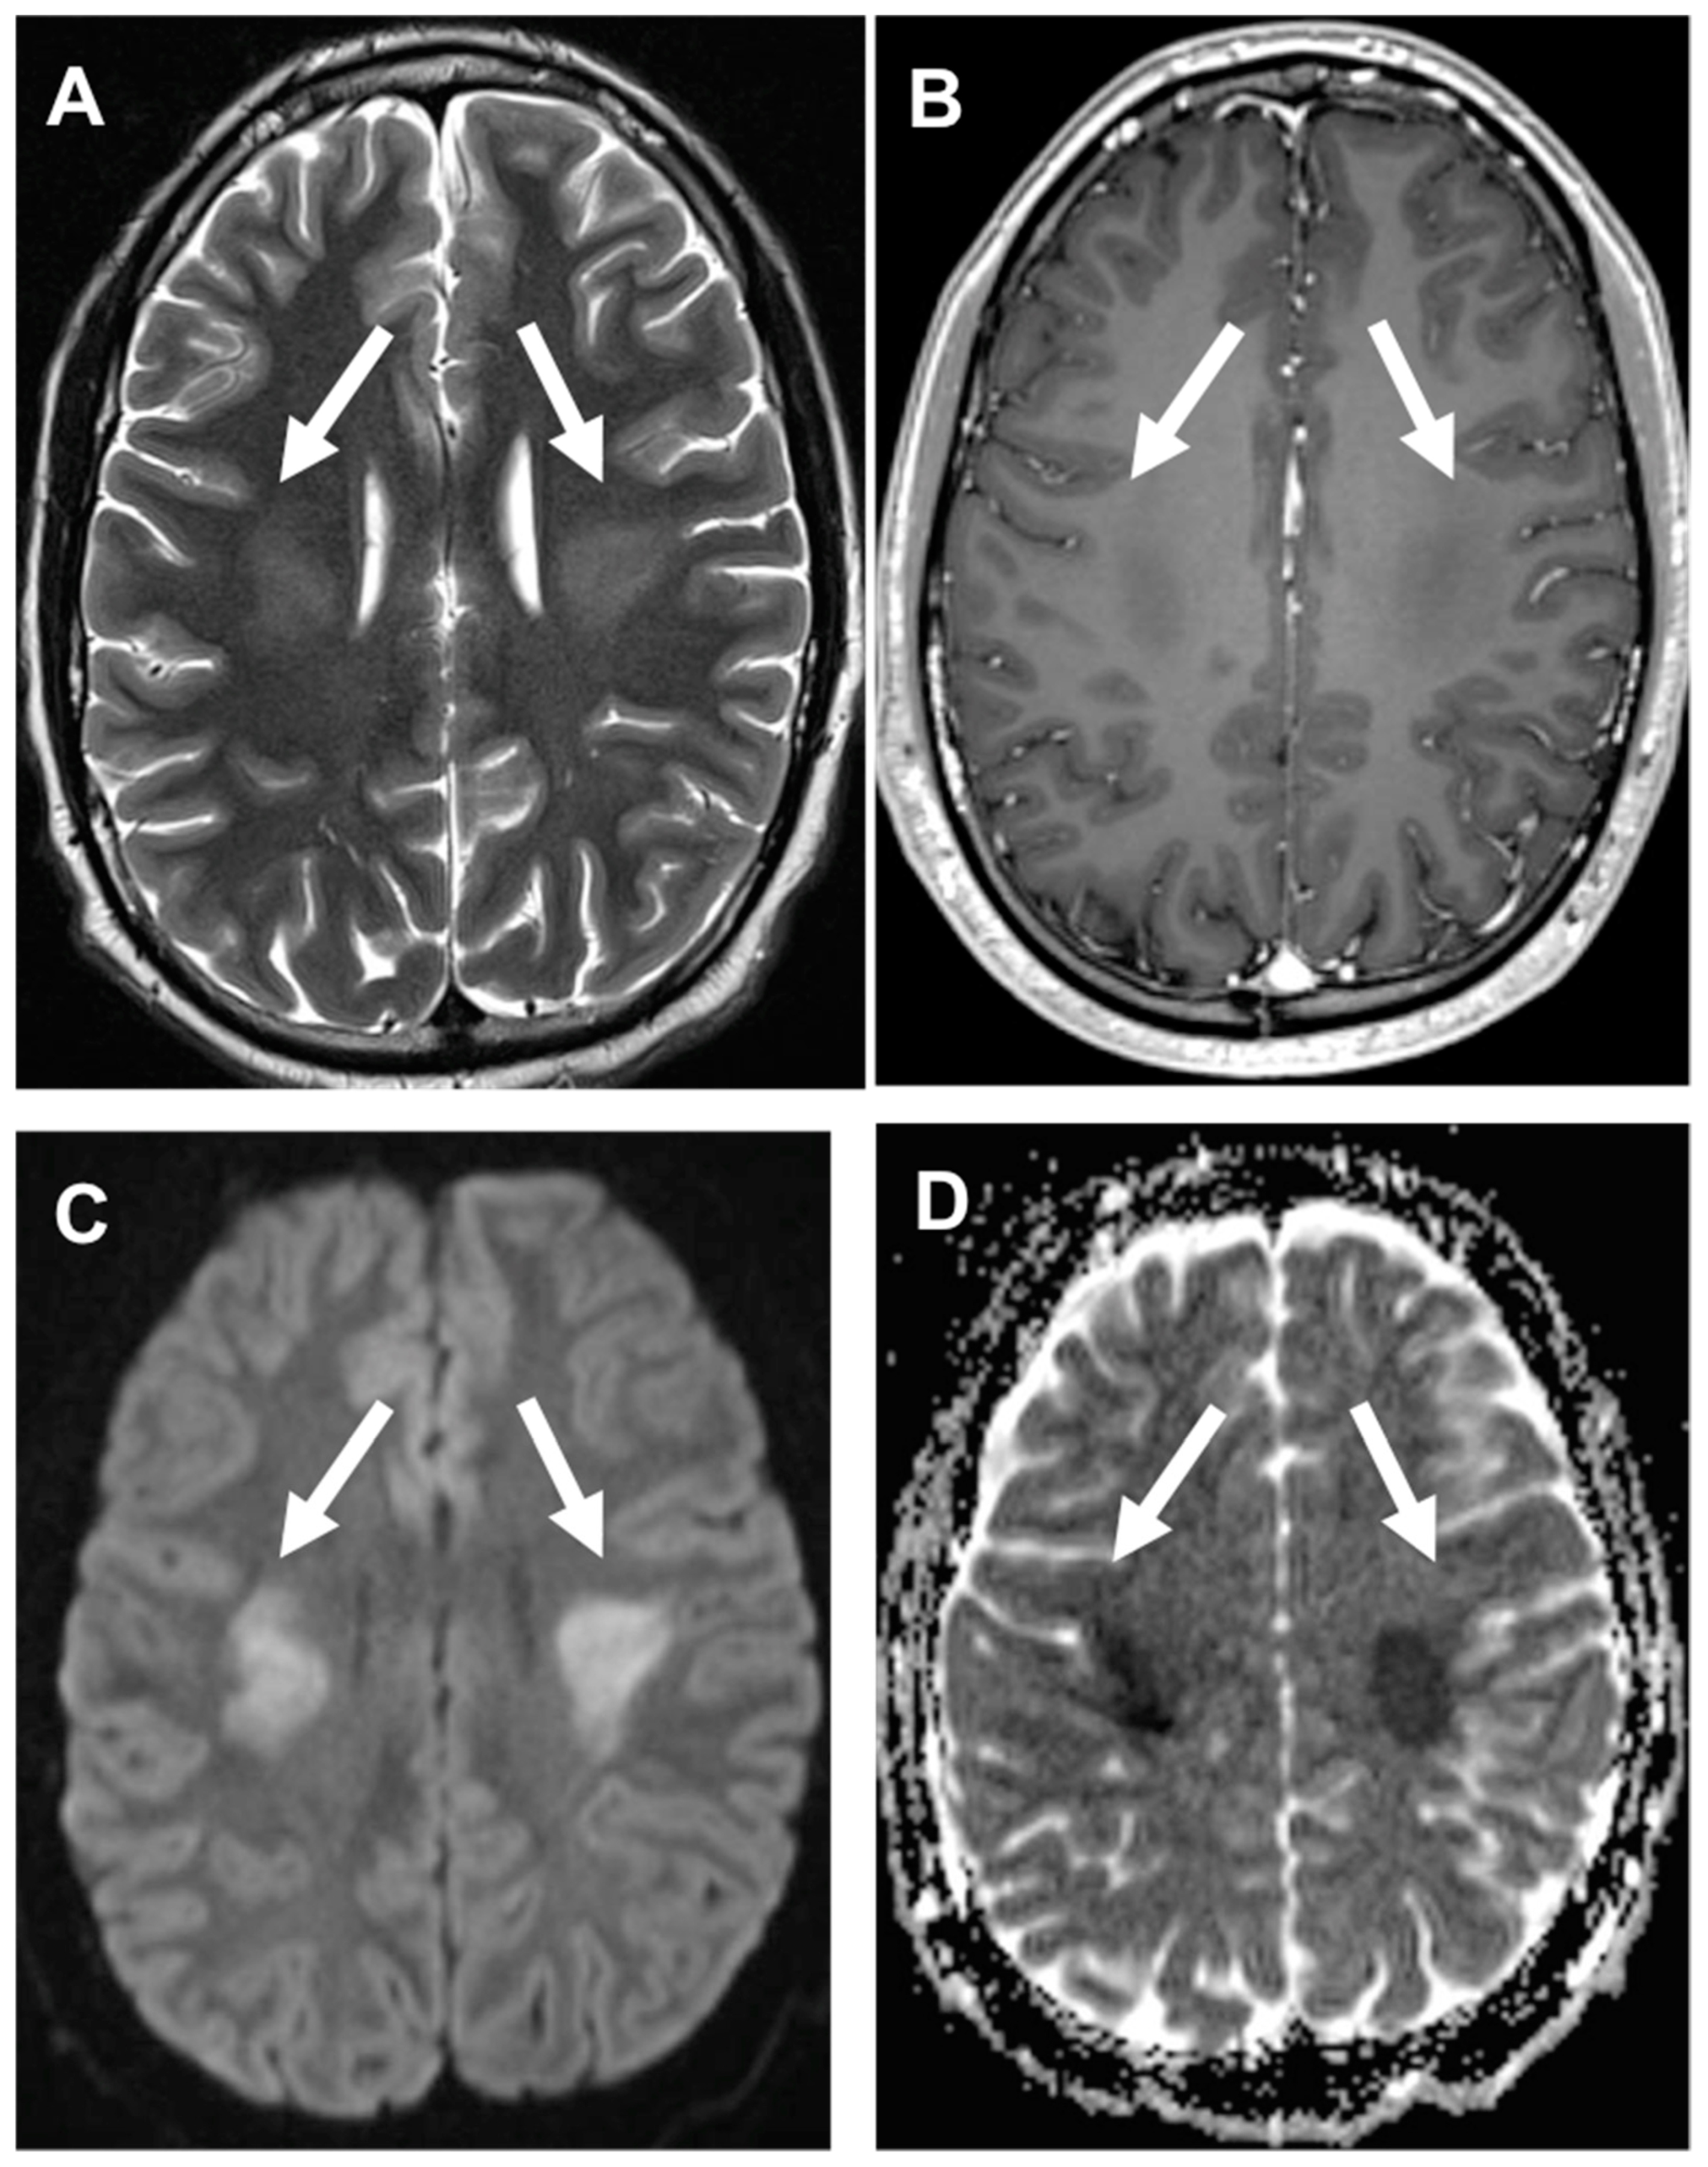

3.3. Stroke-like Migraine Attacks after Radiation Therapy

- Kerklaan, J.P.; Lycklama á Nijeholt, G.J.; Wiggenraad, R.G.J.; Berghuis, B.; Postma, T.J.; Taphoorn, M.J.B. SMART syndrome: A late reversible complication after radiation therapy for brain tumours. J. Neurol. 2011, 258, 1098–1104. [Google Scholar] [CrossRef] [PubMed] [Green Version]

- Rigamonti, A.; Lauria, G.; Mantero, V.; Filizzolo, M.; Salmaggi, A. SMART (stroke-like migraine attack after radiation therapy) syndrome: A case report with review of the literature. Neurol. Sci. 2016, 37, 157–161. [Google Scholar] [CrossRef]

- Armstrong, A.E.; Gillan, E.; Di Mario, F.J. SMART Syndrome (Stroke-Like Migraine Attacks After Radiation Therapy) in Adult and Pediatric Patients. J. Child Neurol. 2014, 29, 336–341. [Google Scholar] [CrossRef]

- Farid, K.; Meissner, W.G.; Samier-Foubert, A.; Barret, O.; Menegon, P.; Rouanet, F.; Fernandez, P.; Orgogozo, J.M.; Allard, M.; Tison, F.; et al. Normal Cerebrovascular Reactivity in Stroke-Like Migraine Attacks After Radiation Therapy Syndrome. Clin. Nucl. Med. 2010, 35, 583–585. [Google Scholar] [CrossRef]

- Black, D.F.; Morris, J.M.; Lindell, E.P.; Krecke, K.N.; Worrell, G.A.; Bartleson, J.D.; Lachance, D.H. Stroke-Like Migraine Attacks after Radiation Therapy (SMART) Syndrome Is Not Always Completely Reversible: A Case Series. Am. J. Neuroradiol. 2013, 34, 2298–2303. [Google Scholar] [CrossRef] [Green Version]

- Ito, H.; Mori, K.; Kagami, S. Neuroimaging of stroke-like episodes in MELAS. Brain Dev. 2011, 33, 283–288. [Google Scholar] [CrossRef] [PubMed]